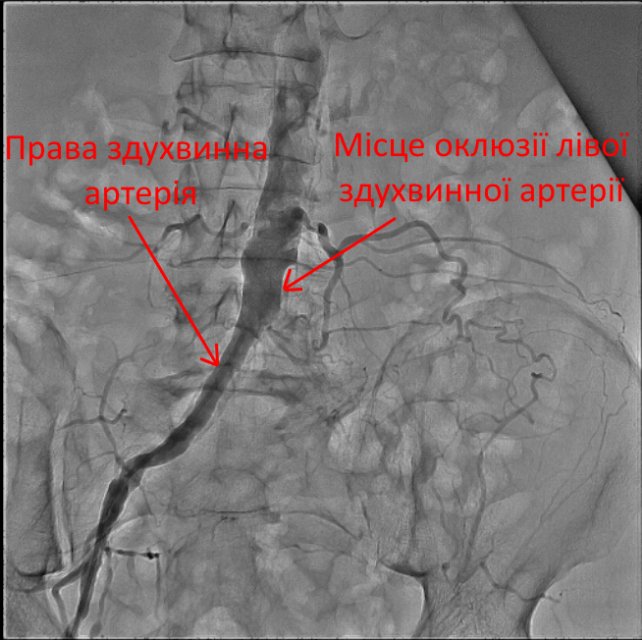

Для встановлення точної причини захворювання провели ангіографію судин нижніх кінцівок.

В результаті дослідження у пацієнта виявили повну оклюзію (закупорку) лівої здухвинної та лівої стегнової артерій.